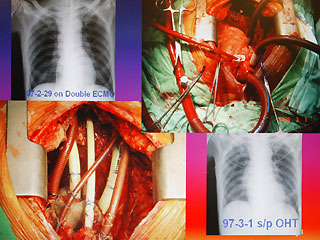

報道說,現(xiàn)年60歲的陳先生,2月初因發(fā)現(xiàn)感染細(xì)菌性心內(nèi)膜炎,致使整顆心臟感染嚴(yán)重,從奇美醫(yī)院轉(zhuǎn)到臺大醫(yī)院之后,經(jīng)家屬同意,決定進(jìn)行全心臟摘除,然后置入葉克膜維持生命。陳先生最后靠著葉克膜撐過16天,奇跡式活下來,于今天順利出院。

臺大醫(yī)院心臟血管外科教授王水深率領(lǐng)團(tuán)隊執(zhí)行這個艱難的手術(shù)。他說,陳先生心臟的三尖瓣膜等處已被細(xì)菌噬光,無法修補(bǔ),最后“走投無路”之下,決定先摘除心臟,而家屬的決定也需要相當(dāng)大的勇氣。

王水深說,摘除心臟時沒人能保證有心臟可換,而靠葉克膜體外維生系統(tǒng)通常也只能維持7天左右,但陳先生靠著兩套葉克膜奇跡式的撐過16天,克服感染及排斥,又能幸運的等到心臟捐贈者,他強(qiáng)調(diào),翻遍文獻(xiàn)可說史無前例。(周先)